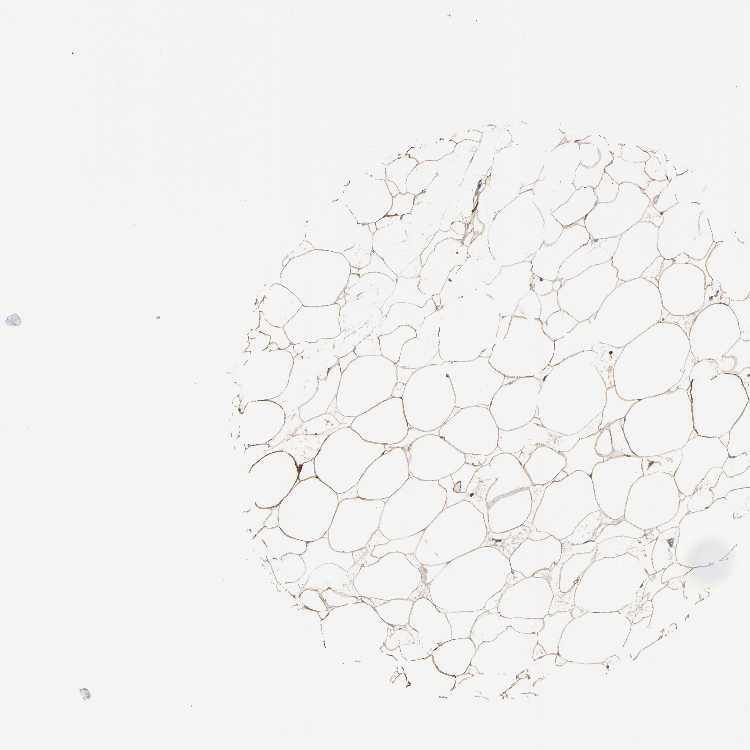

SOFT TISSUE 1 - Antibody stainingi

Antibody staining in the annotated cell types in the current human tissue is reported as not detected, low, medium, or high, based on conventional immunohistochemistry profiling in selected tissues. This score is based on the combination of the staining intensity and fraction of stained cells.

Each image is clickable and will lead to virtual microscopy that enables deeper exploration of all samples and also displays staining intensity scores, fraction scores and subcellular localization as well as patient and tissue information for each sample.

Antibody HPA007636

Fibroblasts Low